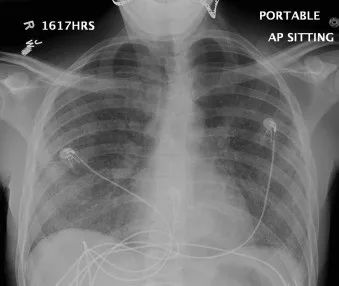

全血白细胞计数为13.4*109/L,血红蛋白8.5g/dL,血小板138/μL,C-反应蛋白28.8(正常值<3.0)。动脉血气分析显示pH值为7.30,PCO2为48.2,PO2为71.8,血培养呈阴性,进行BAL培养(包括细菌培养、病毒培养、真菌培养)。胸部X线及胸部CT显示弥漫性斑片状阴影(图1.2)。颈椎、胸椎和腰椎的CT扫描显示椎体病变(图3.4)。由于脾脏有多处病变,也进行了脾活检(图5)。

图1 胸片:弥漫性双侧间质浸润,无积液或实变